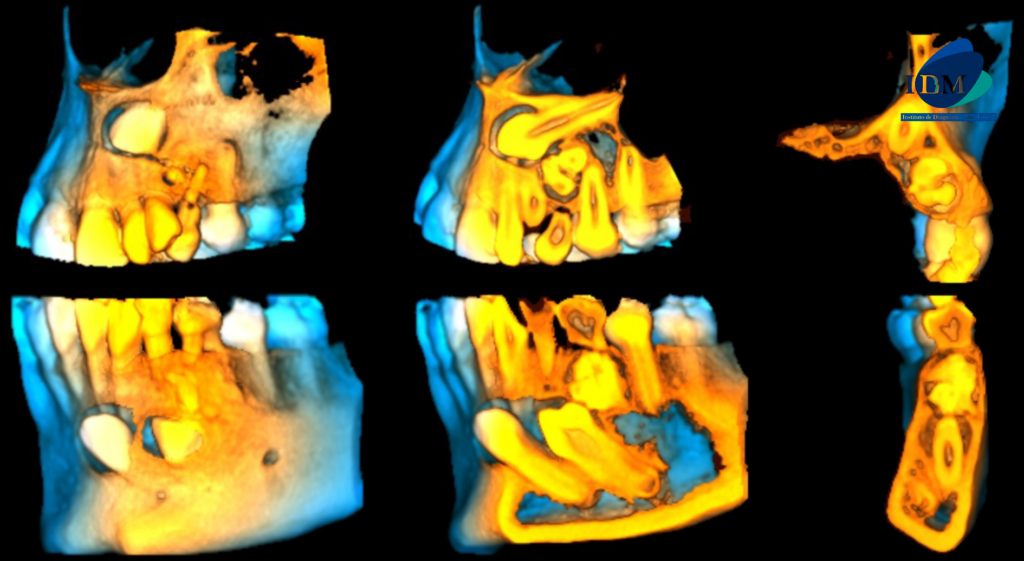

En las reconstrucciones 3D se representa de manera didáctica Odontoma compuesto y complejo (Figura 4).

RECONSTRUCCIÓN 3D

A la evaluación de la tomografía volumétrica (CBCT) en los cortes axiales (Figura 2) y transaxiales (Figura 3), se aprecia imágenes hiperdensas (dentículos) circunscrita con un halo hipodenso, localizada entre los segmentos radiculares de piezas 22 y 24, de limites definidos ocasionando desplazamiento de pieza 23, adelgazamiento de tabla ósea vestibular y palatina compatible con odontoma compuesto. Imagen hiperdensa circunscrita con un halo hipodenso, localizada entre los segmentos radiculares de piezas 73 y 35, de limites definidos, forma irregular, ocasionando el desplazamiento de piezas 34 y 33, adelgazamiento de la tabla ósea vestibular y lingual compatible con odontoma complejo.